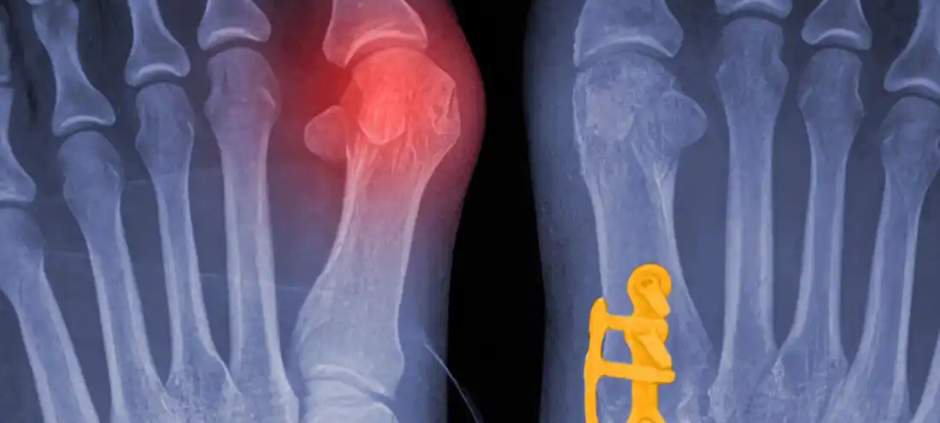

Traditional bunion surgery often involves just cutting the bone to get rid of the bump, which is a bit like mowing a weed without pulling the root. Lapiplasty is different because it addresses the actual cause of the bunion: an unstable joint in the middle of your foot that has rotated out of alignment.

During the procedure, Dr. Khavari uses specialized instruments to rotate the entire bone back into its natural, 3D position. Once the bone is straight, it is secured with small, titanium plates.

This fixes the foundation of your foot rather than just shaving off the surface, which significantly reduces the chance of the bunion ever coming back.